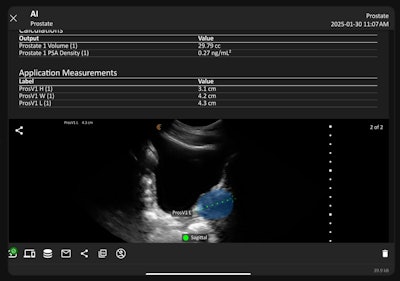

Clarius Prostate AI measures prostate volume from ultrasound exams.Clarius Mobile Health

Clarius Prostate AI is available now with Clarius handheld ultrasound scanners that are customized for urology exams. During an exam, clinicians can activate Prostate AI with a tap in the Clarius App on a smartphone or tablet. The tool automatically highlights the prostate gland and, when the image is frozen, places calipers to measure volume. Clinicians can adjust the calipers manually for precision. The app also calculates prostate-specific antigen (PSA) density using the entered PSA value and measured volume.